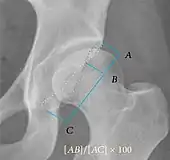

Radiograph of a cam type impingement.

Measurements of impingement on X-ray.[notes 1][20]

MeasurementImageTargetNormal value

Center-edge angle of Wiberg

The superior-lateral coverage of the femoral head.

• >20° (<55 years old)[notes 2]

• <24° (>55 years old)[notes 2]

• >40° indicates overcoverage

Crossing ratio Percentage of acetabular walls crossing. Normal acetabulum is oriented in anteversion. Its value ranges from 15 to 20° in the equatorial plane of the acetabulum and decreases gradually towards the acetabular roof, where normal values range from 0 to 5°. Retroversion of the upper part of the acetabulum has been related with pincer type impingement. In radiography the presence of a “crossover sign” is produced when the posterior wall of the acetabulum crosses the anterior wall before reaching the acetabular roof. It is a sign of acetabular retroversion and it has been linked with overcoverage and pincer impingement. Nevertheless, this sign has been described in 6% of the normal population. Therefore, more important than its presence is the percentage of crossing. <20%

• Higher is significant crossing

Alpha angle

Measured in 45° Dunn view.

Degree of bulging of the femoral head-neck junction: In normal conditions there is a symmetric concave contour at the junction of the femoral head and neck. Loss of this concavity or bone bulging may lead to cam type impingement. The degree of this deformity can be measured by the alpha angle. Although it can be measured in the cross-lateral view, the 45° Dunn view is considered more sensitive and the frog leg view more specific in determining pathologic values.

• Normal: ≤68° in men, ≤50° in women

• Borderline: 69° to 82° in men, 51° to 56° in women

• Pathological: ≥83° in men and ≥57° in women

Femoral head-neck offset

Measured in cross-lateral view.

Offset of the femoral head with regard to most prominent aspect of the femora neck>10 mm

Offset percentage Femoral head-neck offset related to femoral head diameter >0.18

• less indicates high risk of cam type impingement

Tönnis angle Slope of the sourcil (the sclerotic weight-bearing portion of the acetabulum) 0 to 10°

• >10° is a risk factor for instability

• <0° is a risk factor for pincer impingement

Caput-sourcil angle[21] Superior to the Tönnis angle in cases without joint space narrowing or subluxation.[21] The medial point of the sourcil is at the same height as the most superior point of caput femoris. −6 to 12°[21]

• >12° is a risk factor for instability

• <-6° is a risk factor for pincer impingement